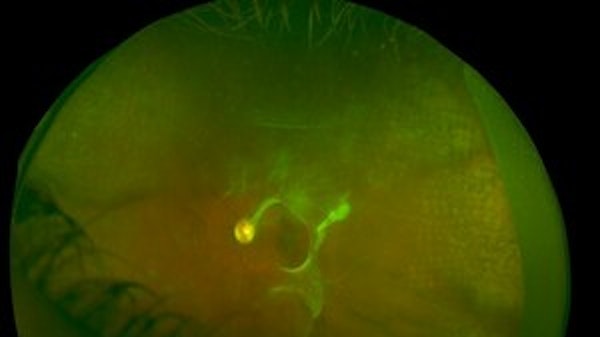

A 41-year-old phakic gentleman with high myopia develops a superonasal detachment that is treated with scleral buckling. A 24-guage pediatric intravenous catheter is introduced into the subretinal space. The subretinal fluid is drained using footpedal-controlled suction provided by the vitrectomy machine. Complete drainage of SRF is achieved using this technique. A general description of the scleral buckle technique can be seen in the video titled "Scleral Buckling Illuminated".